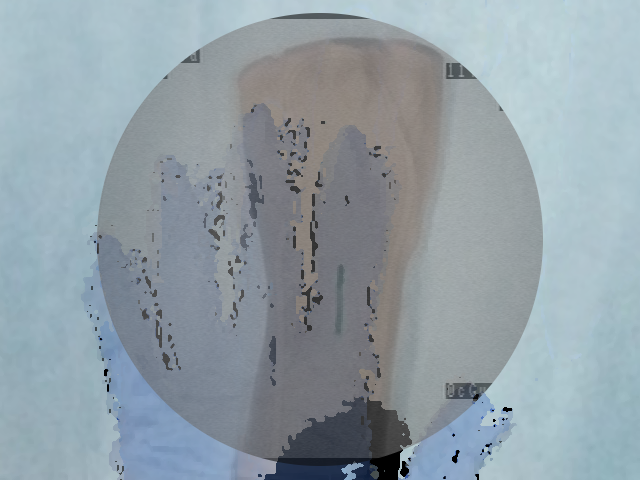

In Figure 5, for each scenario, one selected image Ilayerssubscript𝐼𝑙𝑎𝑦𝑒𝑟𝑠I_{layers} in the sequence can observed with different values of α𝛼\alpha, β𝛽\beta, γ𝛾\gamma and δ𝛿\delta. Each row i𝑖i corresponds to the sequence i𝑖i. From left to right, the layer visualized in Ilayerssubscript𝐼𝑙𝑎𝑦𝑒𝑟𝑠I_{layers} is getting closer to the X-ray source viewpoint. In the column (a), the furthest layer (the X-ray image) is displayed. In the column (b), the second layer (the background), in the column (c), the blending of the front layer with the background, in the column (d), the blending of the three layers and finally, in the column (e), the closest layer is shown. Additional images from the sequences can be visualized in the supplementary video where interaction between the layers by changing the blending values can be observed.

(a) (α,β,γ,δ)=(0,0,1,1)𝛼𝛽𝛾𝛿0011(\alpha,\beta,\gamma,\delta)=(0,0,1,1)

Refer to caption

(b) (α,β,γ,δ)=(0,1,0,0)𝛼𝛽𝛾𝛿0100(\alpha,\beta,\gamma,\delta)=(0,1,0,0)

(c) (α,β,γ,δ)=(0.4,0.6,0,0)𝛼𝛽𝛾𝛿0.40.600(\alpha,\beta,\gamma,\delta)=(0.4,0.6,0,0)

(d) (α,β,γ,δ)=(0.2,0.3,0.5,0.5)𝛼𝛽𝛾𝛿0.20.30.50.5(\alpha,\beta,\gamma,\delta)=(0.2,0.3,0.5,0.5)

(e) (α,β,γ,δ)=(1,0,0,0)𝛼𝛽𝛾𝛿1000(\alpha,\beta,\gamma,\delta)=(1,0,0,0)

(f) Inpainting

Figure 5: Per row i𝑖i, multi-layer image Ilayerssubscript𝐼𝑙𝑎𝑦𝑒𝑟𝑠I_{layers} of one selected frame in the sequence i𝑖i with different blending parameters (α,β,γ,δ)𝛼𝛽𝛾𝛿(\alpha,\beta,\gamma,\delta)

Similar to results from Habert et al. [6], the images resulting from synthesization are not as sharp as a real video image. The area synthesized by our algorithm is approximately 20 cm ×\times 20 cm (C-arm detector size), which is small compared to the wide-angle field of view from the Kinect v2. Reduced to the area of synthesization, the video and depth from Kinect is not of high resolution enough for sharper results. More specialized hardware with smaller field of view and higher resolution RGBD data would solve this problem. Moreover, several artifacts can be seen around the hand and surgical instruments in the synthesized image due to high difference and noise in depth in the RGBD data from the 2 cameras. However, our results demonstrate that our method is working well, since the incision line and cross drawn on the hand model and patient hand are perfectly visible in the recovered background image and can be seen in transparency through the hands and surgical tools in the images of Figure 5-column (c) and (d). In the scalpel sequence (sequence 6) in Figure 5-column (b), it can be seen that the tip of the scalpel is considered as background, this is due to the margin of few centimeters used for background segmentation. In this image, the scalpel is actually touching the skin.